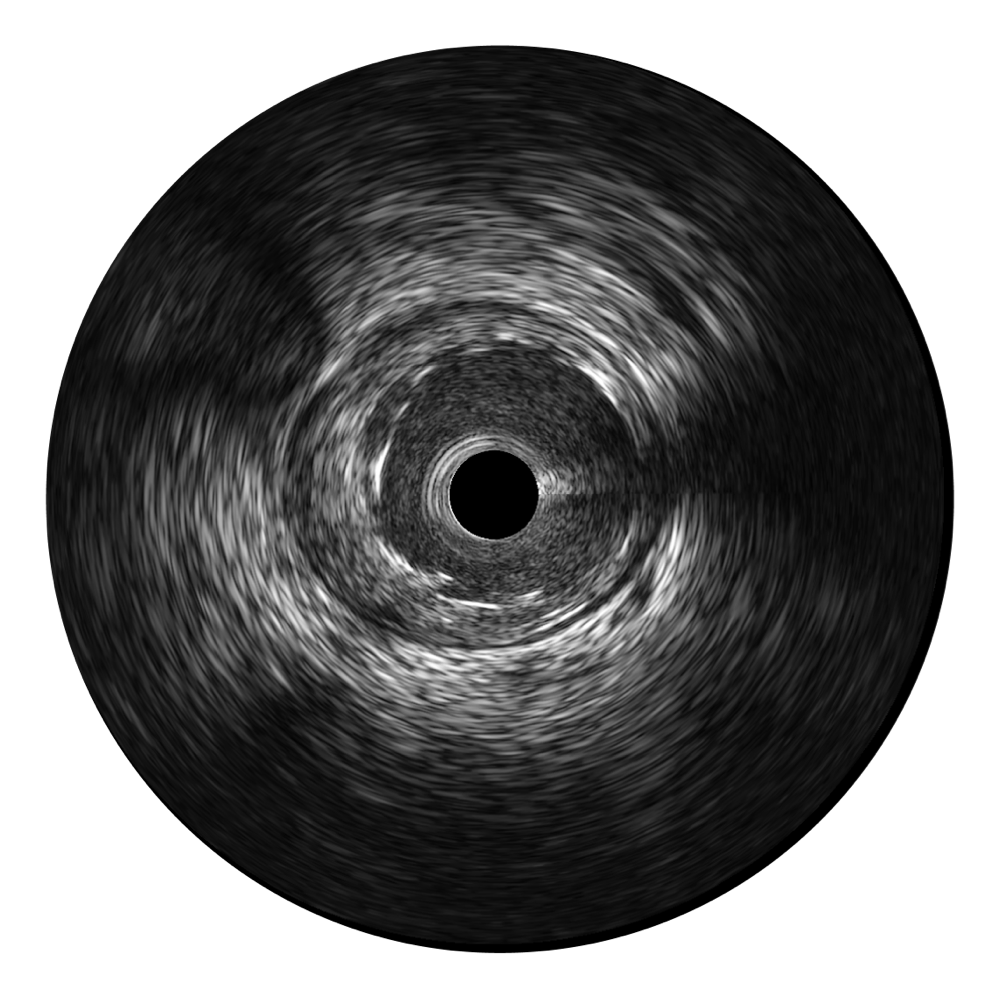

血管内超声(IVUS) 通过对病变程度、性质和累及范围的精确判断,可帮助选择治疗策略和方法,指导介入治疗过程,能够降低主要不良心血管事件,改善预后,在复杂病变介入治疗中用于指导支架置入的优势更为明显。血管内超声(IVUS)已成为精准心血管介入治疗的“金标准”。

宽频成像,兼具高分辨力和更大穿透深度

16877太阳集团超宽频成像技术覆盖20-80MHz1或20-90MHz2频率范围, 提供优异的分辨力同时也保证充足的穿透深度